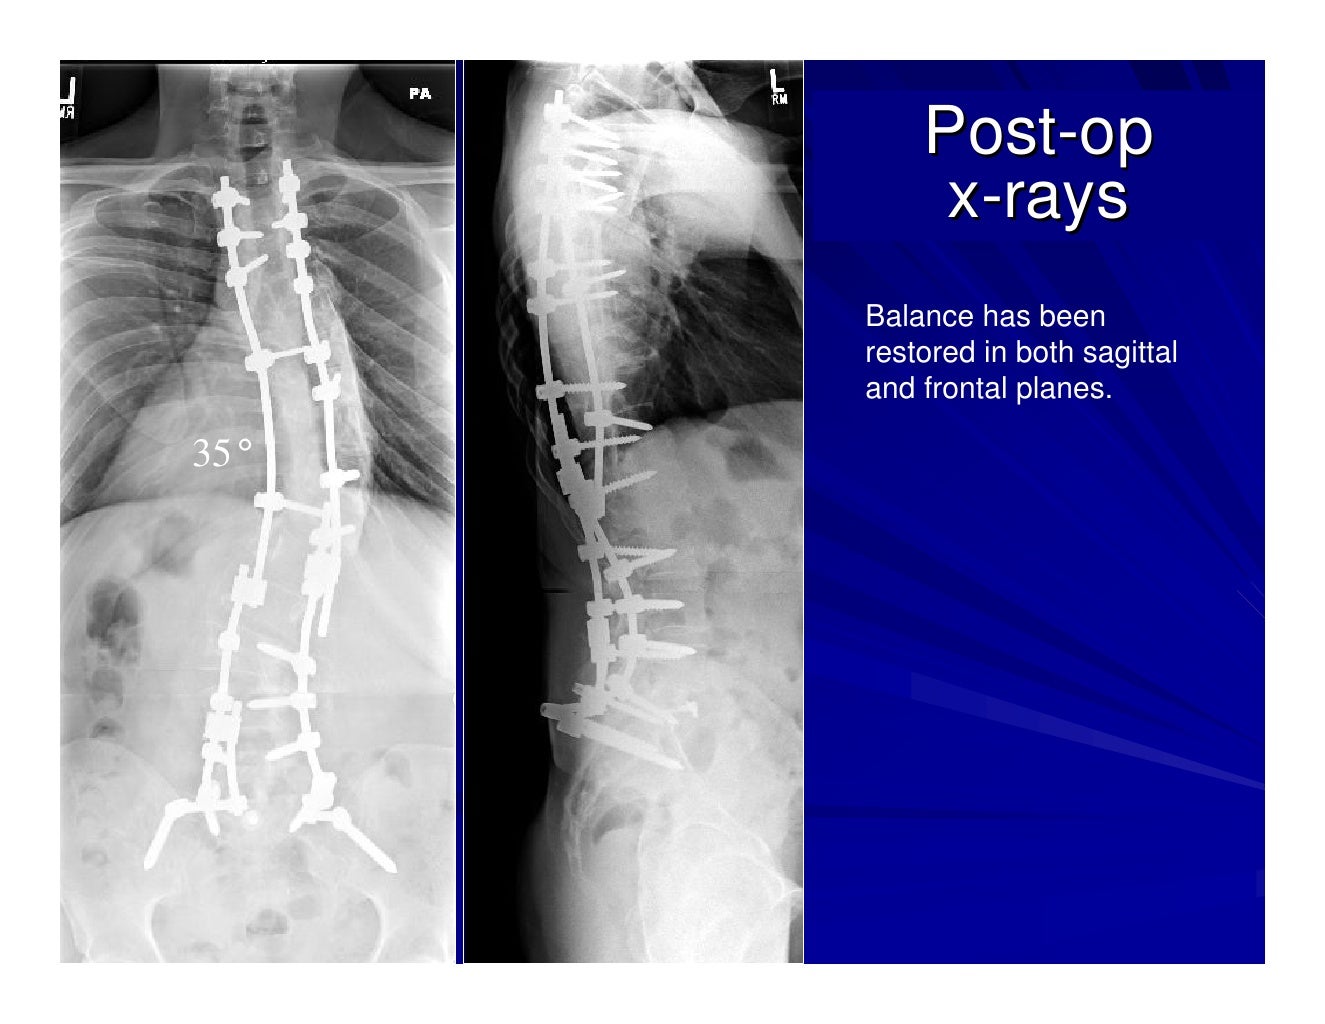

Case Review 1 42 year old make with Adult Scoliosis Harrington Rod Harrington Rods Removal It's attached to the spine with the goal of holding it in a straighter position so its vertebrae can't become more tilted over time. Once the rod is removed,. Scoliosis spinal fusion surgery is performed by inserting a harrington rod with a ratcheting system along the concave part of the curve and attaching it to the spine with two hooks. Harrington Rods Removal.

Case Review 1 42 year old make with Adult Scoliosis Harrington Rod Harrington Rods Removal Harrington rods can bend, break loose from the wires, or worse, break completely in two, necessitating further surgical intervention and removal of the rod. Once the rod is removed,. A wide array of hardware is commonly used in instrumented spinal surgery. It's attached to the spine with the goal of holding it in a straighter position so its vertebrae can't. Harrington Rods Removal.

Case Review 1 42 year old make with Adult Scoliosis Harrington Rod Harrington Rods Removal It's attached to the spine with the goal of holding it in a straighter position so its vertebrae can't become more tilted over time. A wide array of hardware is commonly used in instrumented spinal surgery. A harrington rod for scoliosis is instrumentation used in spinal fusion; Harrington rods can bend, break loose from the wires, or worse, break completely. Harrington Rods Removal.

Case Review 1 42 year old make with Adult Scoliosis Harrington Rod Harrington Rods Removal A wide array of hardware is commonly used in instrumented spinal surgery. Once the rod is removed,. A harrington rod for scoliosis is instrumentation used in spinal fusion; This information is for patients who have had surgical correction of. Scoliosis spinal fusion surgery is performed by inserting a harrington rod with a ratcheting system along the concave part of the. Harrington Rods Removal.

Case Review 1 42 year old make with Adult Scoliosis Harrington Rod Harrington Rods Removal This information is for patients who have had surgical correction of. A harrington rod for scoliosis is instrumentation used in spinal fusion; It's attached to the spine with the goal of holding it in a straighter position so its vertebrae can't become more tilted over time. A wide array of hardware is commonly used in instrumented spinal surgery. Scoliosis spinal. Harrington Rods Removal.